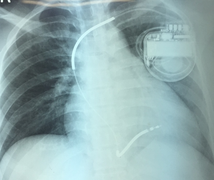

Một người phụ nữ trẻ mắc bệnh yếu cơ tim gây rối loạn nhịp tim hiếm gặp, có thể đột tử bất cứ lúc nào vừa được các bác sĩ Bệnh viện Chợ Rẫy cứu chữa.